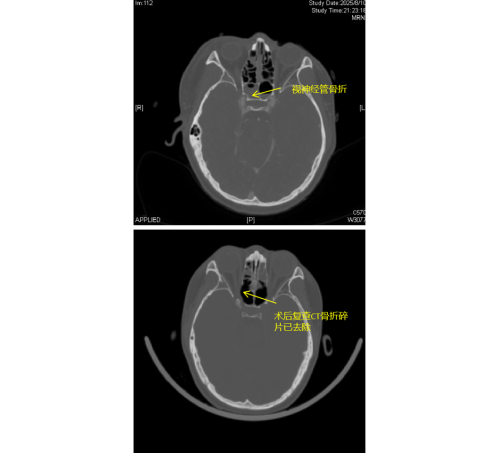

患者李琦(化名)是一名17岁少年,夜间骑电动车不慎撞上路边栏杆,随即出现右眼视力骤降、头痛头晕等症状,被120紧急送入91短视频 (南华大学附属长沙中心医院)急诊科。经检查发现,李琦存在颅底多处骨折、面颅多发骨折,尤其危急的是右侧视神经管骨折,碎裂的骨片直接压迫视神经及邻近的颈内动脉,导致右眼瞳孔散大、对光反射消失,视力完全丧失,病情极为危重。

由于视神经管周围解剖结构复杂,上方毗邻前颅底,下方紧邻颈内动脉和海绵窦,稍有不慎就可能导致脑脊液鼻漏、视神经断裂甚至颈内动脉破裂出血等严重后果,因此视神经的特殊位置被视为“手术雷区”。加之操作空间小,手术难度大,对于医生而言是一个巨大的挑战。视神经与鼻窦相邻,用鼻内镜经鼻窦进行视神经管减压手术,视野清楚、损伤最小。在手术过程中,康晓明医生利用高清鼻内镜,精准地清除了压迫视神经的骨折碎片,有效降低了神经压力。

手术完成后即刻观察到李琦右眼对光反射恢复灵敏,经过系统的治疗,其右眼视力已恢复至0.1,术后效果显著。目前,李琦正在进一步康复治疗中。此类高难度手术的成功,不仅展现了医院在多学科协作和急重症救治方面的综合实力,也为复杂颅底外伤患者带来了新的希望。